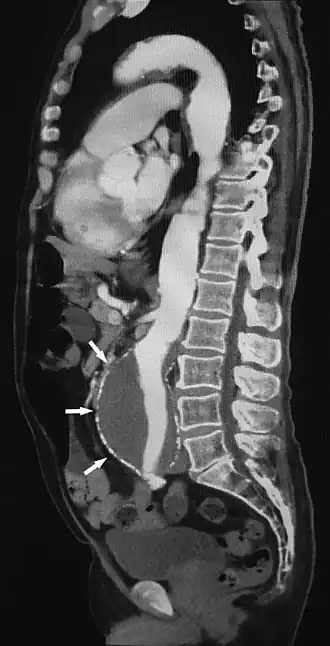

Sagittal thin slice of a computed tomography angiography abdominal aortic aneurysm (AAA) (arrows) | |

Aorta and great arteries

CTA can be used in the chest and abdomen to identify aneurysms in the aorta or other major blood vessels. These areas of weakened blood vessel walls that bulge out can life-threatening if they rupture. CTA is the test of choice when assessing aneurysm before and after endovascular stenting due to the ability to detect calcium within the wall.[3] Another positive of CTA in abdominal aortic aneurysm assessment is that it allows for better estimation of blood vessel dilation and can better detect blood clots compared to standard angiography.[4]